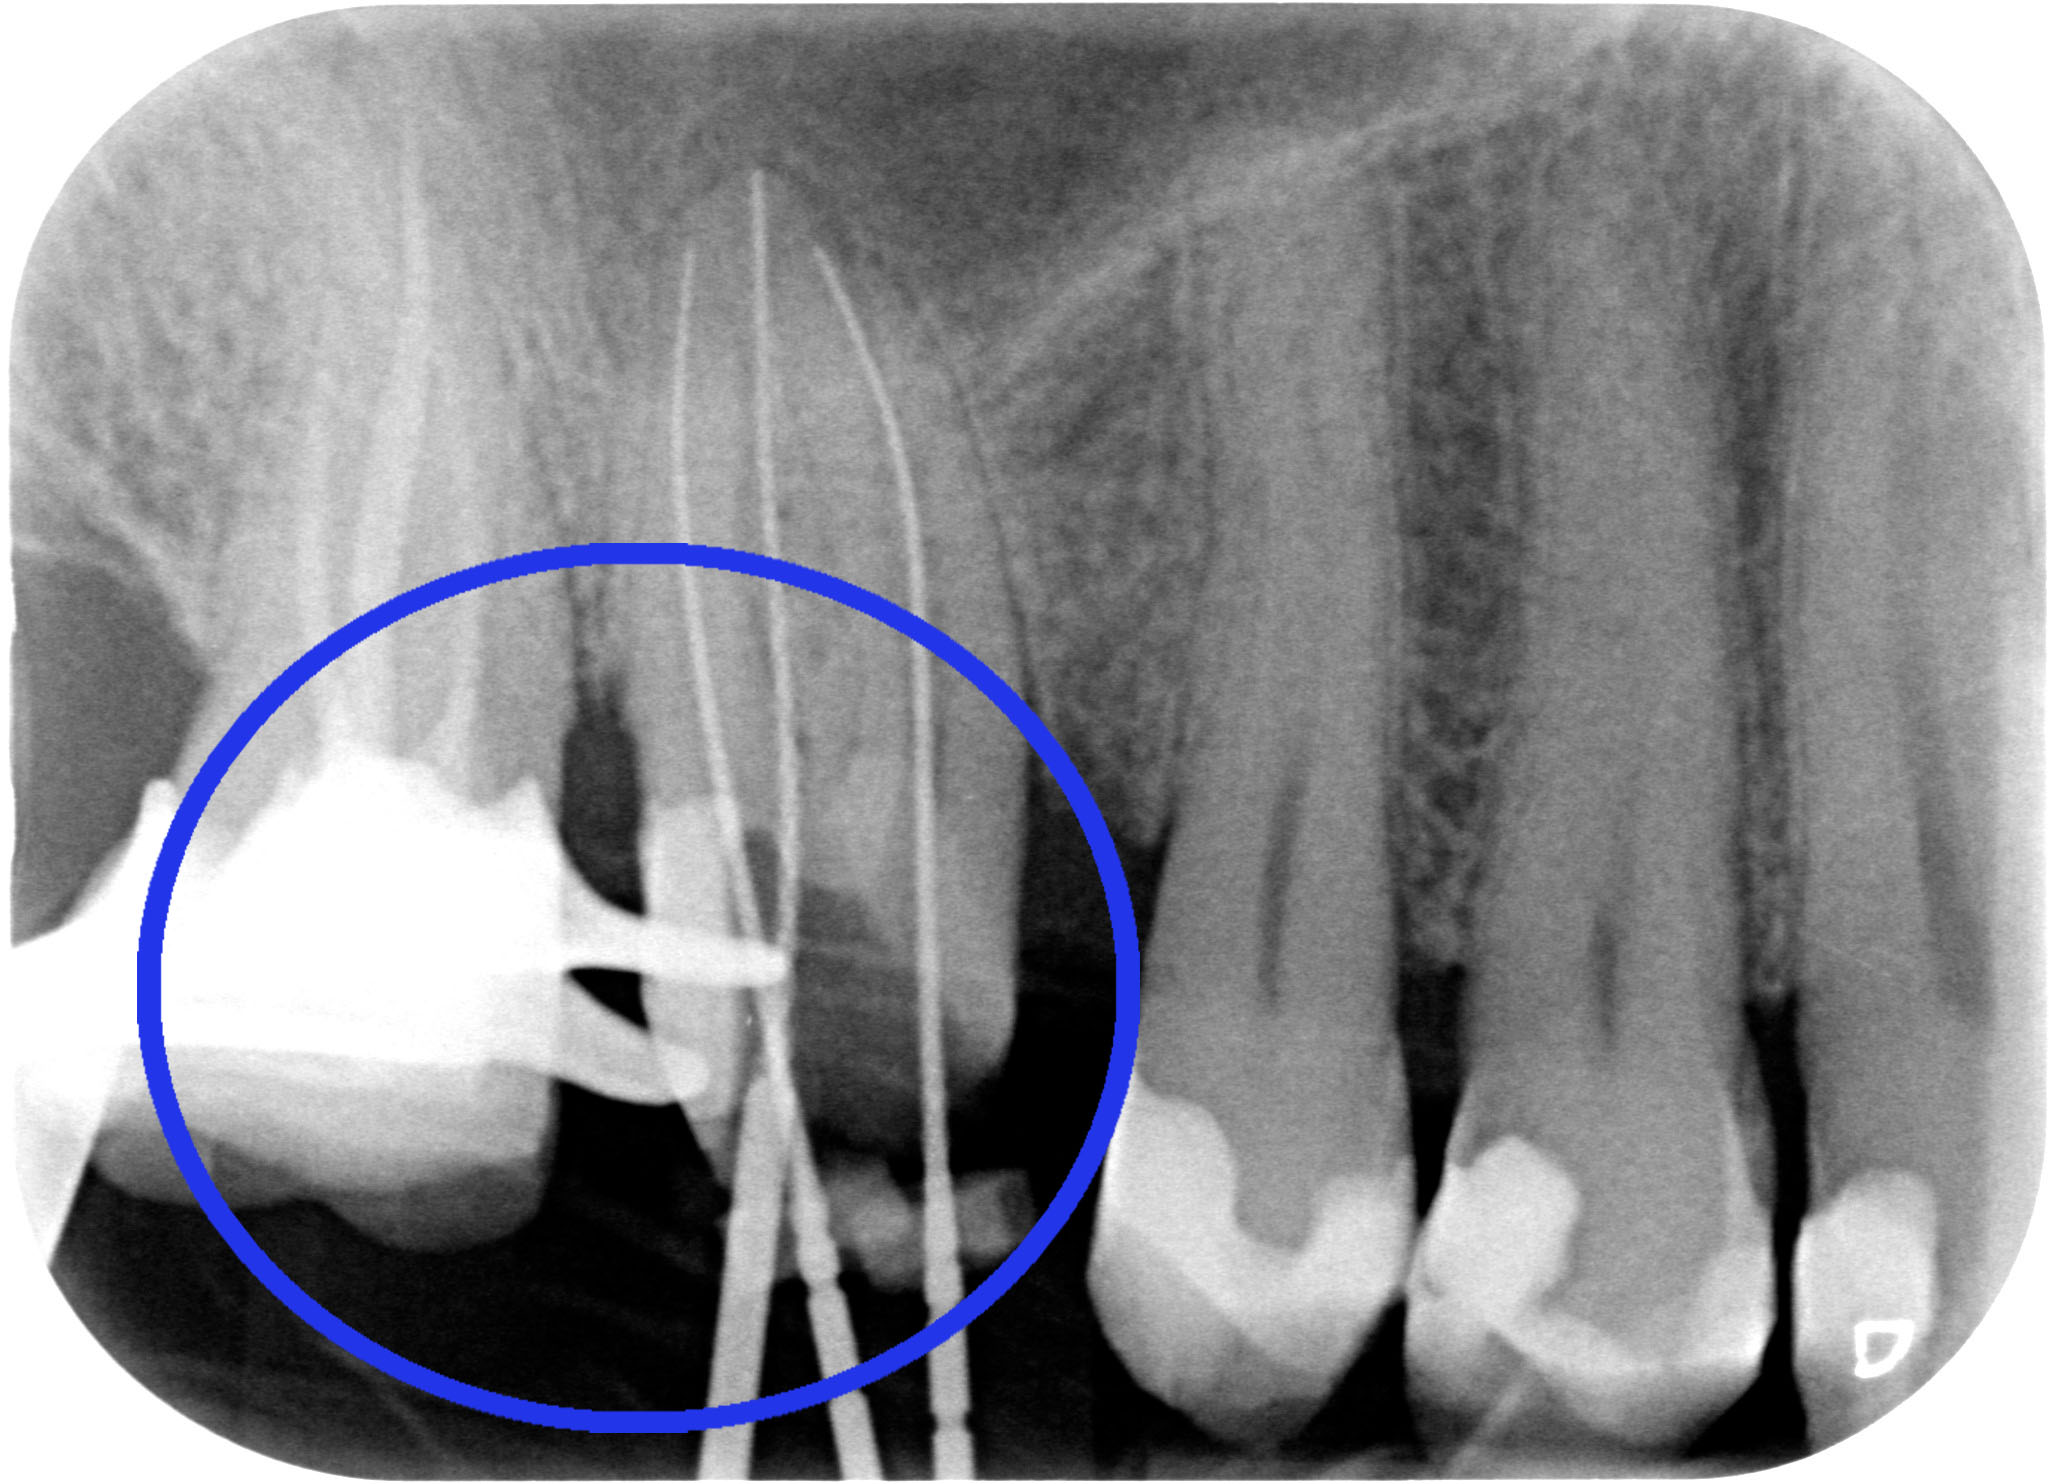

ESEGURE UN CORRETTO RESTAURO PROTESICO

Allungamento di corona clinica 004

“Hei hei guarda un po’ lì cosa ha combinato questo?! Una tacca sul dente dietro!!”

Allungamento di corona clinica 005

Beh caro amico, la fresa tra i due denti ci deve passare e se le due radici sono troppo vicine bisogna creare lo spazio per una papilla interdentale sana e non sofferente, dove poter mettere un filo retrattore (anzi due) alla presa dell’impronta. Quindi sì, lo ammetto: una tacca di qua e una tacca di là!

PS: l’allungamento di corona clinica non vuol dire aprire la papilla fresare un po’ di osso interprossimale e chiudere! Quello tecnicamente si chiama creare un difetto parodontale iatrogeno.